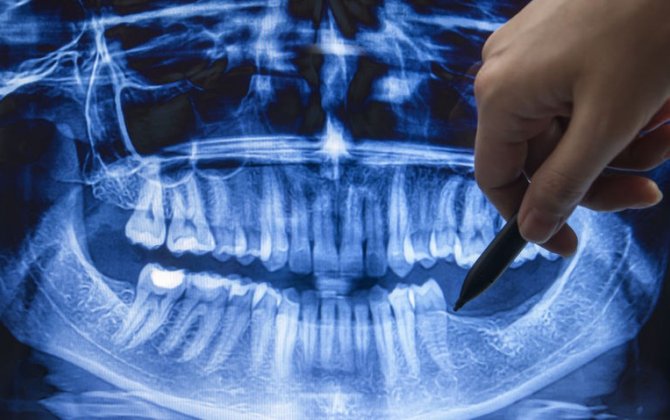

Uzun illərdir dişlərini itirən insanlar yalnız implant və ya protezlərlə çıxış yolu tapırlar. Lakin Yaponiyadan gələn xəbərlər bu sahədə inqilab vəd edir.

Nəşr yazır ki, Tokio və Kioto universitetlərinin alimləri dişlərin təbii şəkildə regenerasiyasına imkan verən preparat və biotexnologiyalar üzərində çalışaraq mühüm nailiyyət əldə edib. Məqsəd - insan orqanizmində yeni dişlərin yetişdirilməsini təmin etməkdir.

Alimlər müəyyən ediblər ki, USAG-1 adlı protein dişlərin təbii inkişafını bloklayır. Onun fəaliyyətini xüsusi monoklonal anticisimlər vasitəsilə dayandırmaqla, orqanizmdə yeni dişlərin böyüməsi mümkün olur. Təcrübələr əvvəlcə gəmiricilər və xoruzquyruqlarda aparılıb, nəticədə əlavə dişlər formalaşıb və ciddi yan təsir müşahidə edilməyib.

Bundan başqa, embriyon hüceyrələri üzərində aparılan araşdırmalar göstərib ki, epitel və mezenximal hüceyrələr birləşdirildikdə, yeni diş toxuması yaranır və transplantasiya olunduqda əvvəlki ilə eyni funksiyaya malik dişlər yetişir.

Əgər bu texnologiya uğurla təsdiqlənərsə, stomatologiyada ən ağrılı prosedurlar - implant, protez və cərrahi müdaxilələr arxa plana keçəcək. Bununla yanaşı, biotexnologiyanın daha geniş hədəfləri də var: gələcəkdə yalnız diş deyil, bədənin digər orqan və toxumalarının da laboratoriyada yetişdirilməsi mümkün ola bilər.